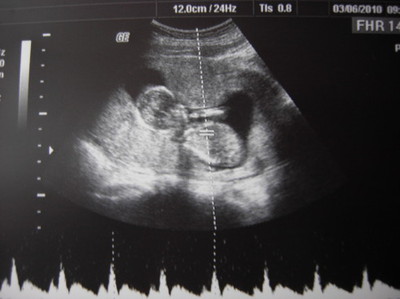

(圖/懷孕週期:14W)

可以很明顯看到你的脊椎和四肢了。醫生還特別檢查你的頸部透明帶,很正常。把拔偷偷觀察躺在診療室的馬麻,她看著螢幕中的你時,臉上因不舒服而產生的痛苦表情頓時消失,取而代之的是慈祥與溫柔的微笑。